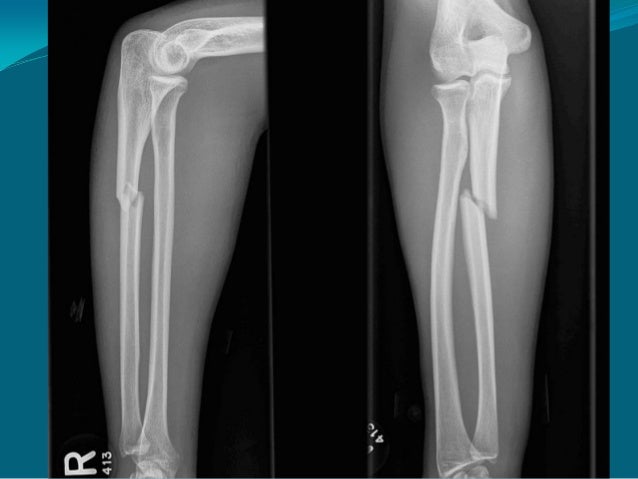

Cận lâm sàng: X-quang

Chụp toàn bộ

cẳng tay ở tư thế

ngửa, lấy cả

khớp khuỷu và

khớp cổ tay.

Chụp ở hai bình

diện: thẳng...

15. 15. Cận lâm sàng: X-quang Chụp toàn bộ cẳng tay ở tư thế ngửa, lấy cả khớp khuỷu và khớp cổ tay. Chụp ở hai bình diện: thẳng và nghiêng.